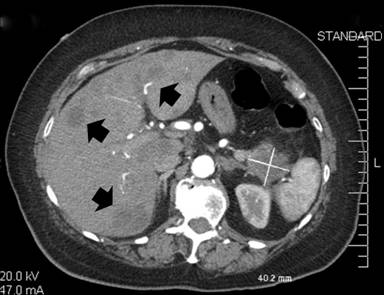

A 61-year-old female with history of hypertension, hyperthyroidism and depression presented with a one-day history of bilateral painless bluish discoloration of multiple toes. She was not on anticoagulants or any drugs known to induce vasospasm. She denied cocaine, tobacco or alcohol use. Family history was significant for colon cancer in her father. At admission, she was afebrile, with a blood pressure of 118/76 mmHg, a regular heart rate of 112 beats per minute and a respiratory rate of 22 per minute. Abdominal examination revealed hepatomegaly. She had bilateral bluish-black discoloration of multiple toes suggestive of a dry gangrene (Figure 1). The rest of her physical examination was unremarkable. New T-wave inversions in the inferolateral leads were revealed at electrocardiography. Initial blood tests demonstrated moderately elevated cardiac and liver enzymes (Table 1). Doppler study of lower extremities revealed bilateral thromboses of peroneal veins without any evidence of arterial occlusive disease. A transthoracic echocardiogram was normal. CT angiogram of chest and abdomen showed acute bilateral subsegmental pulmonary emboli and multiple hypodense hepatic lesions, along with a 3 cm mass arising in the pancreatic tail (Figure 2). This prompted therapeutic anticoagulation with unfractionated heparin. Over the course of the next 48 hours, she developed dysarthria, limb weakness and altered sensorium. A magnetic resonance angiogram of the head showed diffuse embolic infarctions with a large area of hemorrhagic transformation in the left temporal lobe (Figure 3). Extensive laboratory testing for an underlying hypercoagulable state was negative and serum CA 19-9 level was markedly elevated (Table 1). Fine needle aspiration biopsy from the liver lesions was consistent with metastatic adenocarcinoma (Figure 4). The diagnosis of metastatic pancreatic cancer was made based on the presence of a pancreatic mass, positive tumor markers and histopathology findings. Subsequently, the patient’s family opted for a transfer of care to a specialized oncology center, where she eventually expired several weeks later.

Figure 2. Axial contrast enhanced abdominal computed tomography scan demonstrating multiple hypodense hepatic lesions (black arrows) and a 3 cm mass in the pancreatic tail (white cross). |